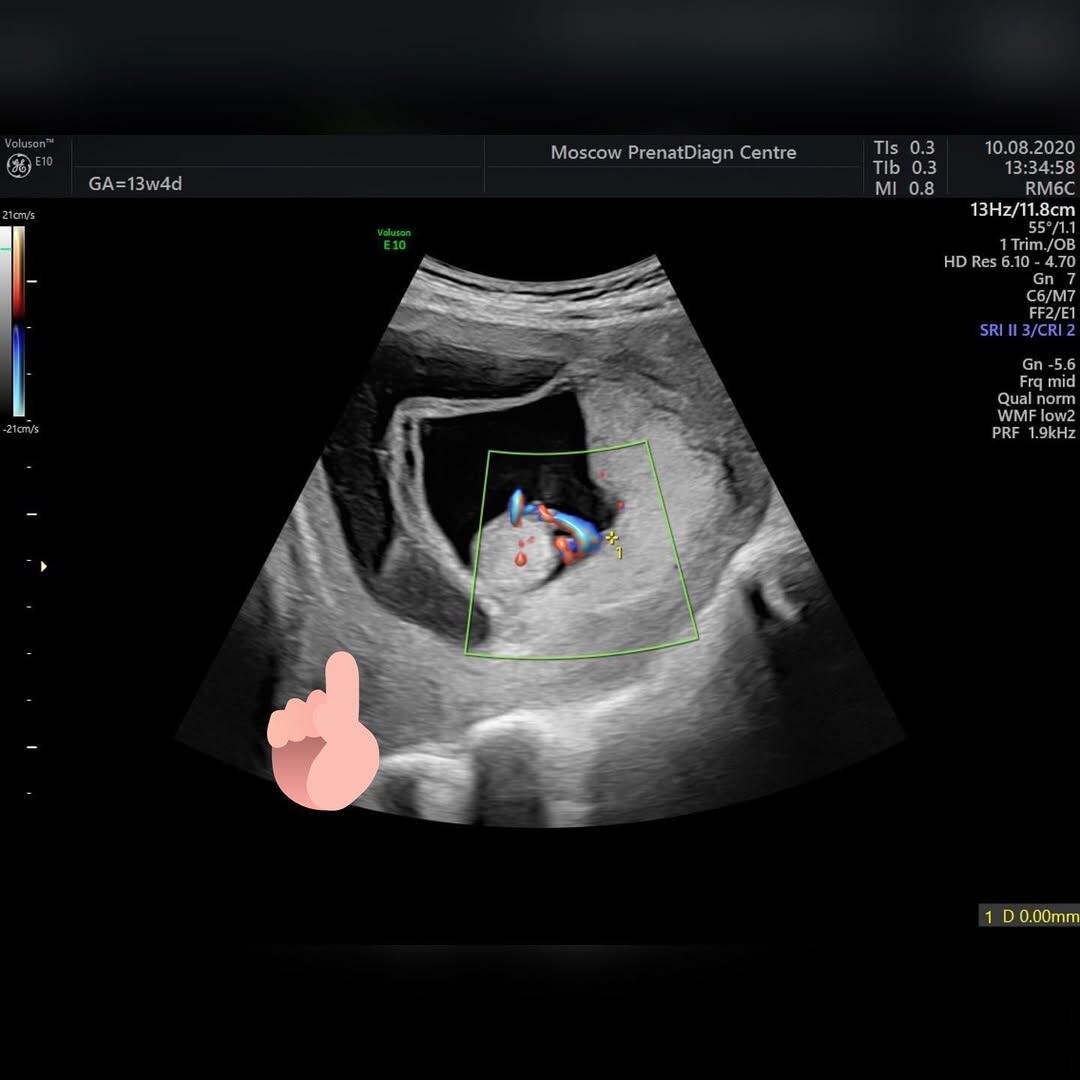

Картинка на УЗИ выглядит страшненько. Плодное яйцо буквально плавает в луже крови, но плод при этом бодр и весел. Это не ретрохориальная гематома, которая отслаивает и изгоняет плодное яйцо, а хориоамниотическая сепарация — ХАС.

👉Листайте галерею, чтобы посмотреть, как выглядит ХАС.

Если оболочки слились, но по каким-то причинам вновь отделились друг от друга, речь идет о хориоамниотической сепарации — ХАС. Это явление, когда происходит разделение уже сформировавшейся мембраны на плацентарную (хориальную) и плодовую (амниотическую) оболочки.

Самопроизвольные полные ХАС встречаются крайне редко. Как правило мы видим расслоение оболочки на небольшом протяжении, при этом клинических проявлений может и не быть. В некоторых случаях имеют место кровянистые выделения из половых путей, иногда очень обильные, которые пугают беременную и лечащего врача. Конечно, наличие кровянистых выделений — грозный признак, но в случаях частичной спонтанной ХАС прогноз в большинстве случаев благоприятный.

Расслоение оболочки — это не отслойка, не ретрохориальная гематома и, как бы это странно не звучало, не признак угрожающего выкидыша. Терапия препаратами прогестерона ничего не изменит. То, что мы видим в виде обильных кровотечений — это результат смешивания небольшого количества крови, выделяющейся при расслоении мембран и секрета амниотической оболочки.